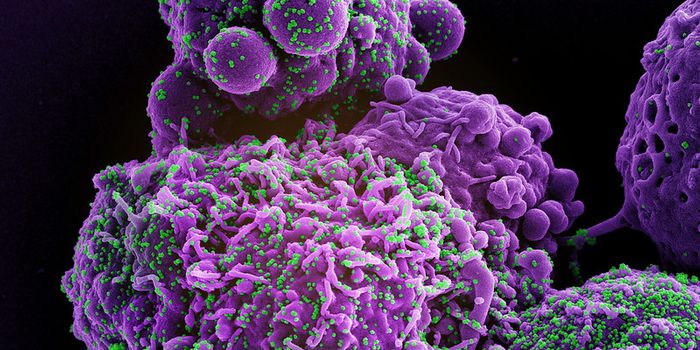

JUL 19, 2016CancerA decade-old technology to arm the immune system to fight cancer is now being adapted to fight HIV, one of the most pern ...